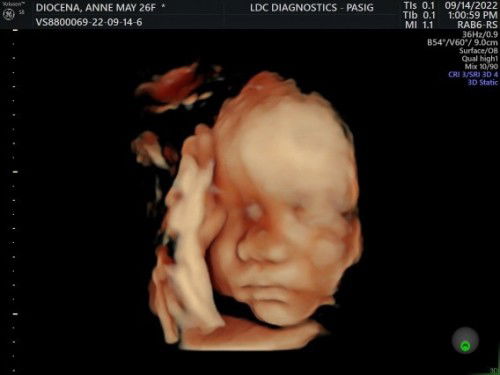

Share ko lang po yung experience ko sa LDC Diagnostics - Pasig where I got my 4D Ultrasound at a very affordable price. Dahil may promo sila until the end of September, 950php lang po babayaran with 3 printed pictures. Sobrang accomodating pa ng mga staff at super linis ng facility nila na akala mo nasa Hotel ka lang or what. Worth it din yung 950 kasi di titigilan ni Doc ai baby hanggat walang malinaw na kuha ☺️ Sa mga gustong magpa 4D, try nyo po sa LDC located in Rosario, Pasig. #NovemberBabies